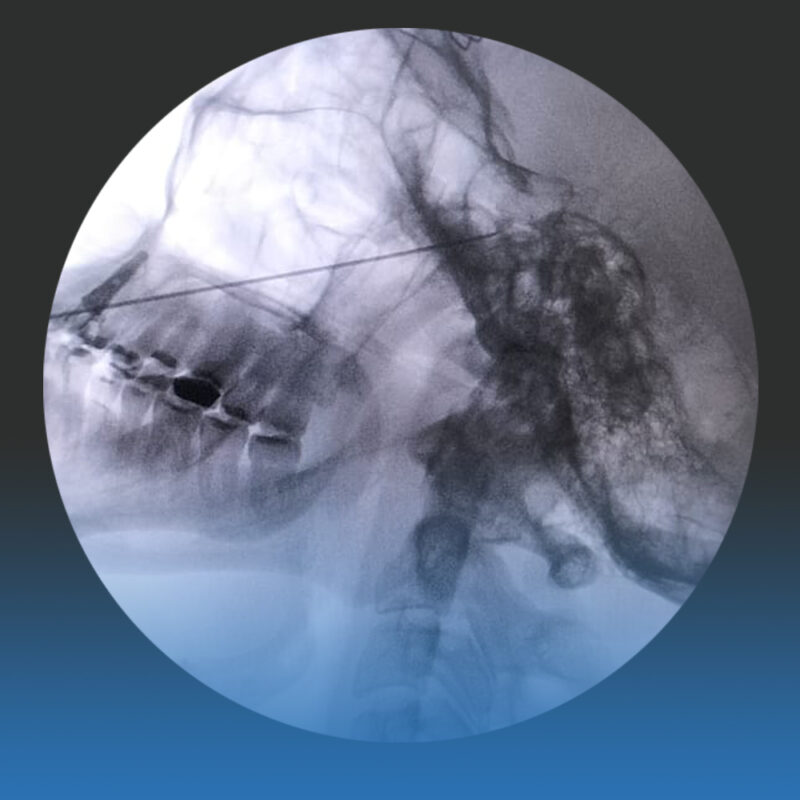

2. Procedimientos mínimamente invasivos: Indicados cuando el dolor persiste o los medicamentos causan efectos secundarios. Incluyen rizotomías percutáneas y radiofrecuencia para interrumpir selectivamente la transmisión del dolor.

3. Cirugía microvascular: Recomendada en casos específicos donde un vaso sanguíneo comprime el nervio trigémino. Este Tratamiento de Neuralgia del trigémino busca aliviar la presión y proporcionar un alivio duradero.